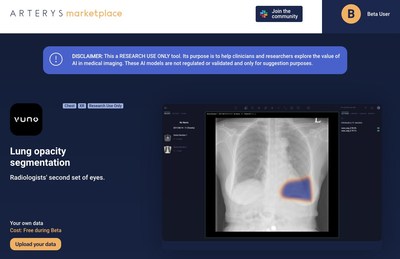

Arterys Arms Clinical AI Developers With a Web Platform for Medical Image Analysis to Accelerate Collaborative Research in the Fight Against COVID-19

SAN FRANCISCO, April 22, 2020 /PRNewswire/ -- AI researchers around the world are developing and publishing algorithms that can detect COVID-19 in medical images, including CTs…